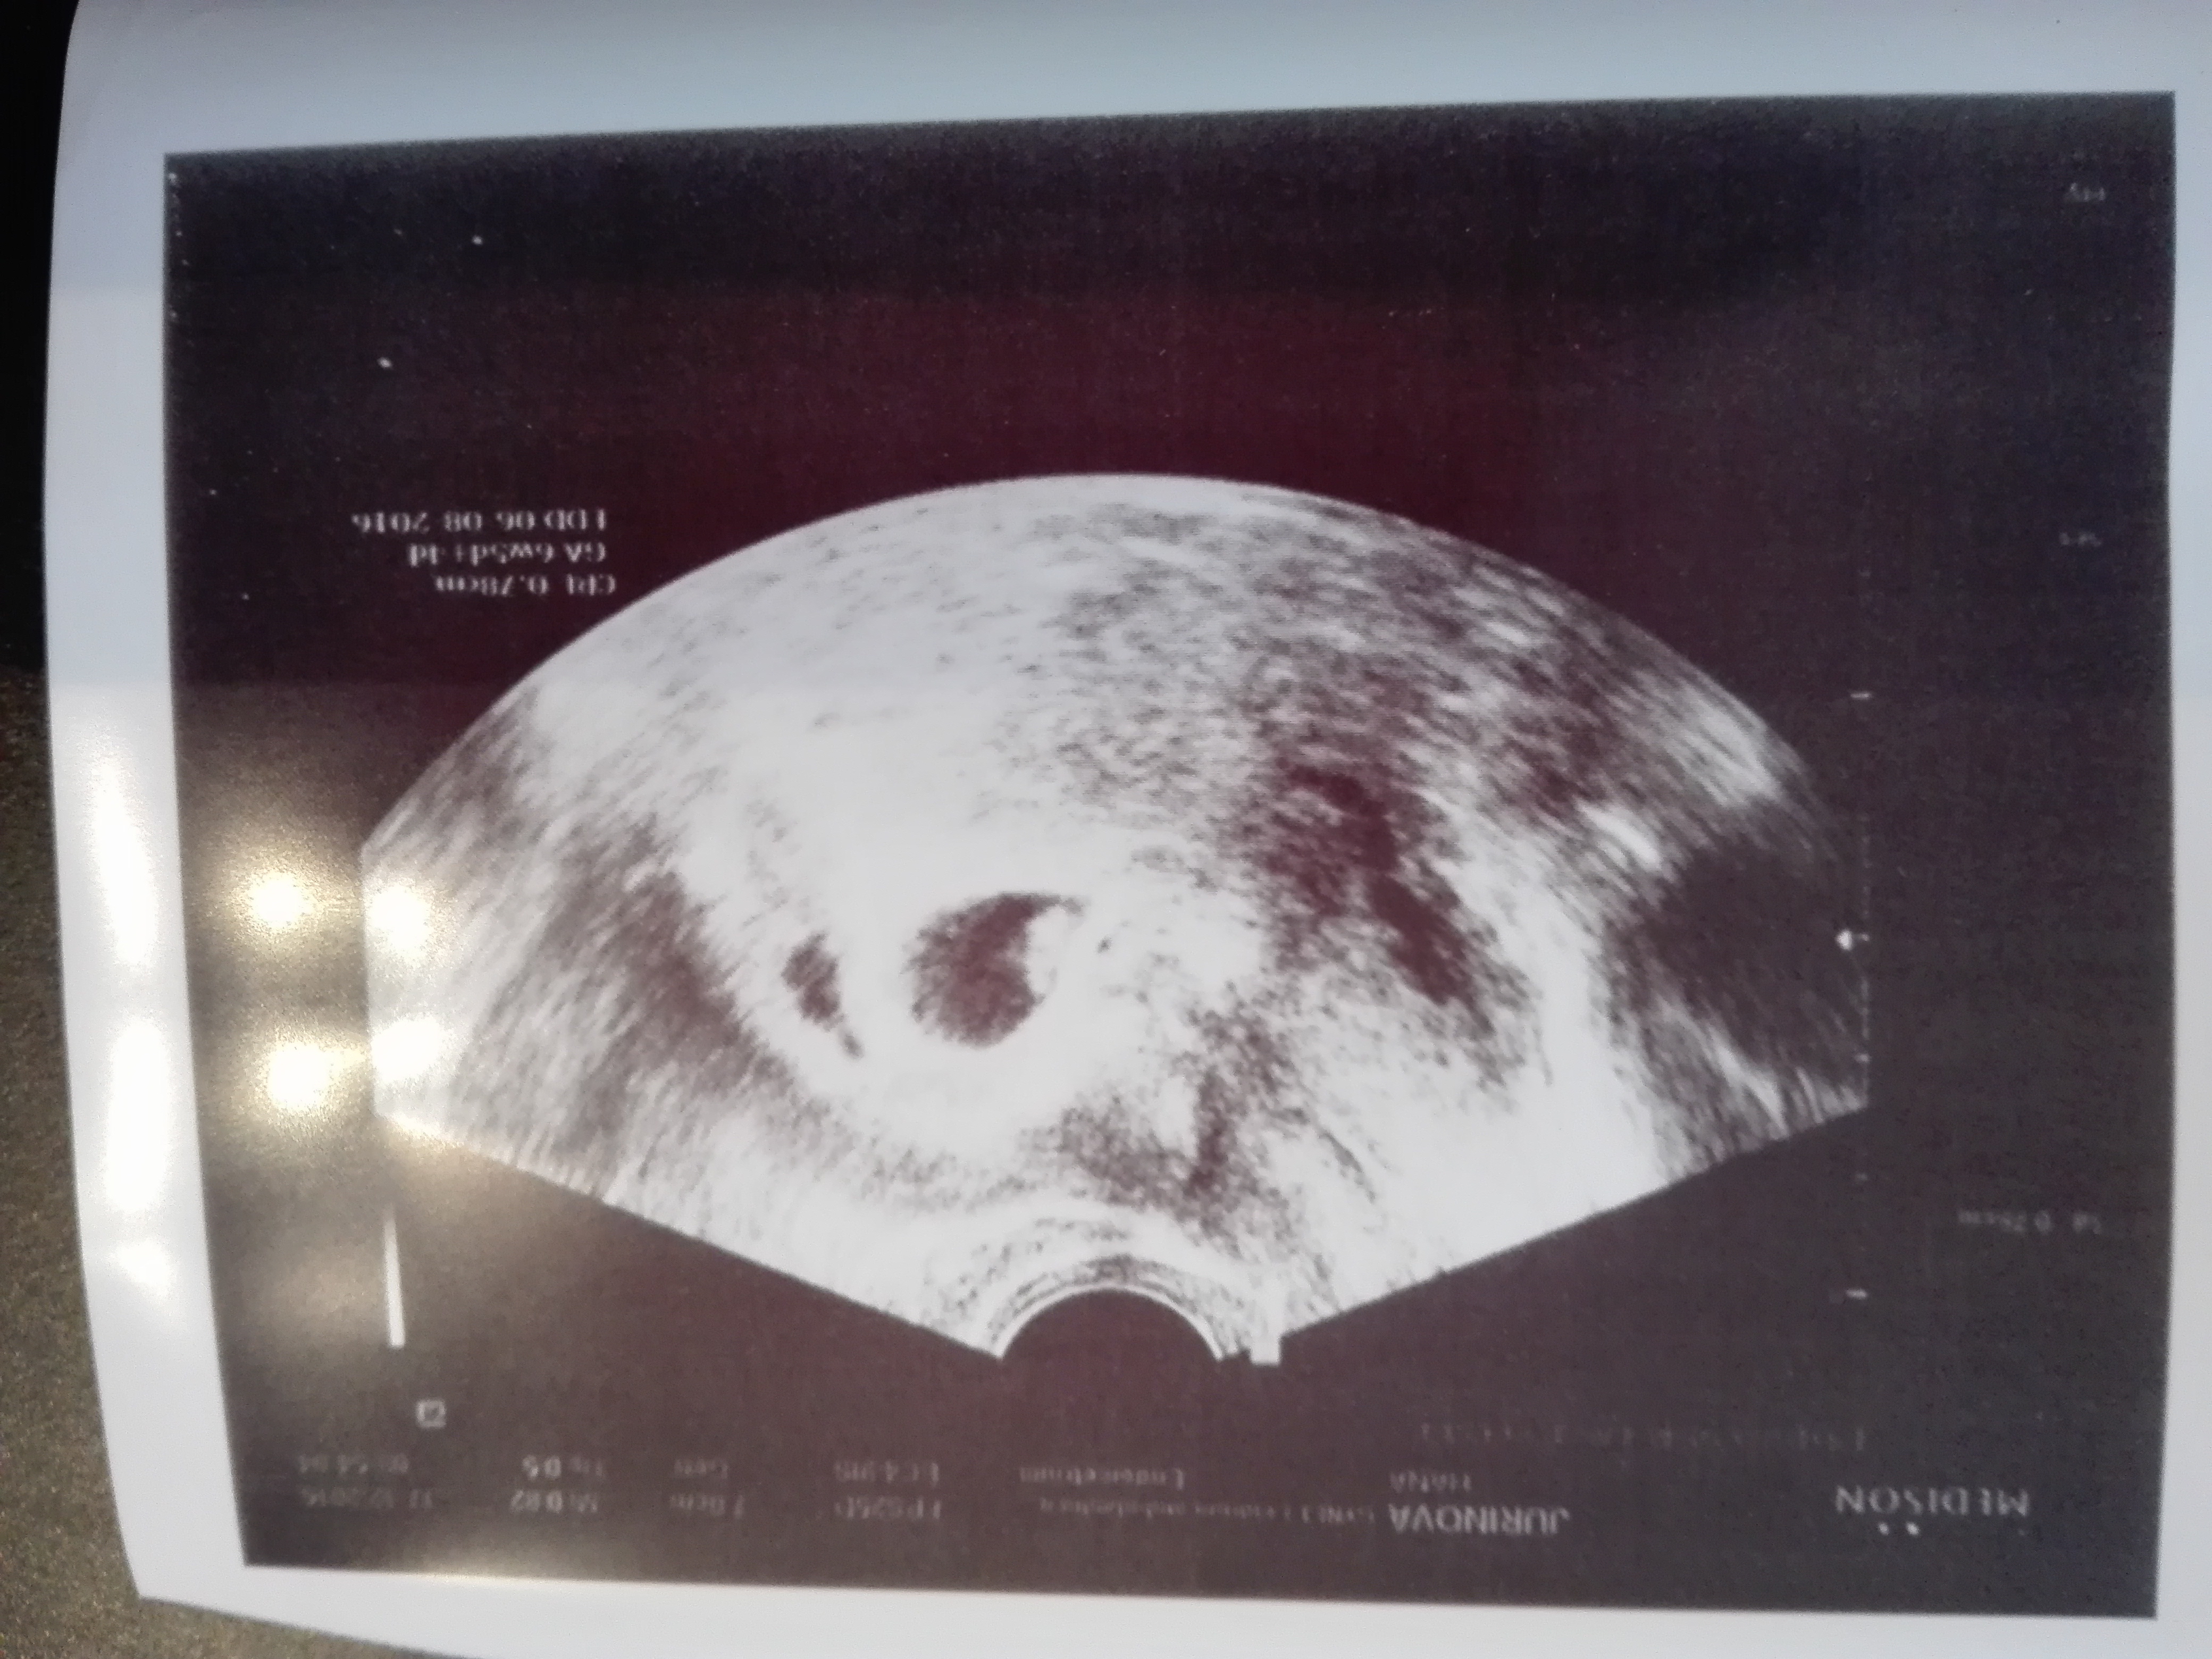

ahoj, vcera jsem byla na UZ, a mam potvrzeny 1 plod, 7tt. Přítel me ale vydesiil, ze jsou tam jsou 2. doktorka sice chvili tak taky vypadalla, ale nakonec jen 1. Co si o fotce myslite vy?

18.12.2015 9:49Je tam jen jedno, druha dutinka muze byt a)mizejici, b) usti vejcovodu napriklad, co si pamatuju jak mi dr pri ultrazvuku ukazovali...